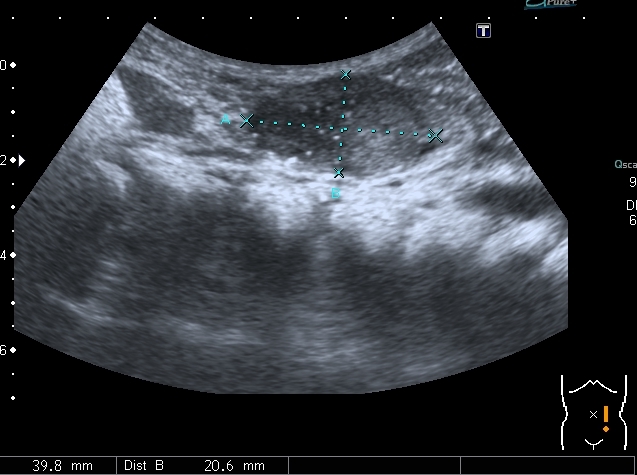

Увеличены парааортальные лимфатические узлы.